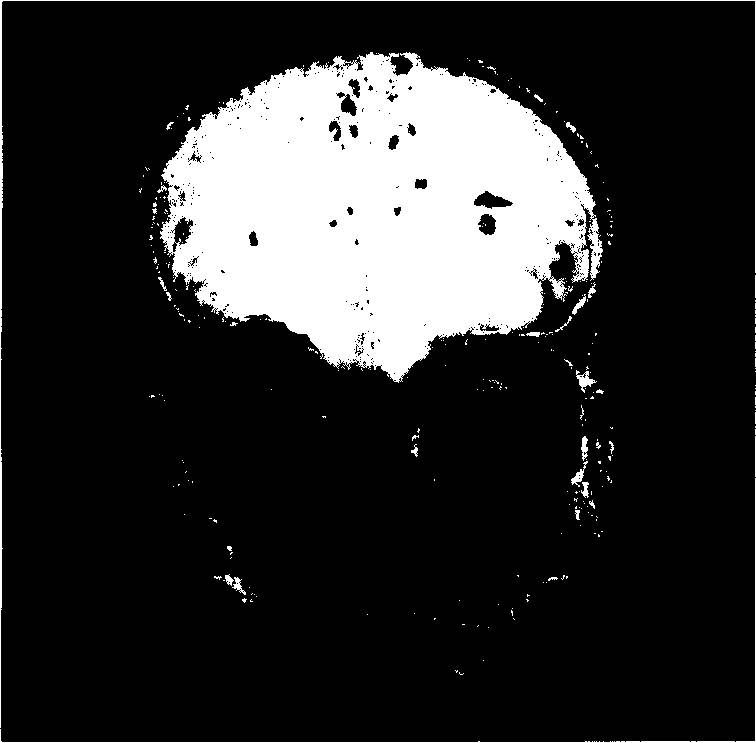

Давайте взглянем на коронарный срез через лобные доли мозга.

Мы увидим, что сложнорасположенные изгибы коры головного мозга, мягко говоря, неравновысотны, и что в петлях срезов любой из извилин находится substantia alba (белое вещество). Это то, что видно глазу при простом фронтальном срезе (илл. 21а).

Отпрепаровка покажет, что снизу в кору вплетаются миллиарды волокон мозолистого тела ( corpus callosum) – структуры сверхнежной и сверхсложной (илл. 21Ь). Все это, естественно, при добросовестной экстирпации частично удаляется вместе с корой или фатально поражается.

Илл. 21а. Фронтальный срез мозга. Видны сложнорасположенные изгибы

коры головного мозга, в петлях срезов любой из извилин находится

substantia alba (белое вещество) (по Блинкову)

Илл. 21Ь. Волокна мозолистого тела (по Блинкову)